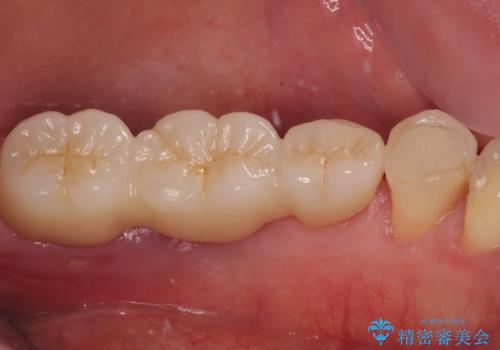

ブリッジから膿が出る 奥歯のインプラント治療

上顎は最後臼歯が欠損しているため、ブリッジの土台は抜歯し、元々の欠損部にインプラントによる補綴治療を行うこととしました。

支台歯の骨欠損は予想以上に大きく、即時荷重インプラント部への影響が心配されましたが、無事に最短期間で治療を終えることができました。